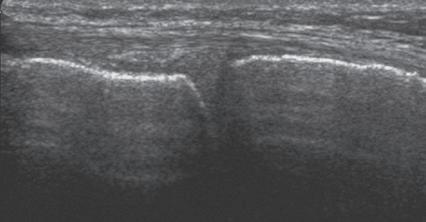

such artifact is anisotropy 6 When a tendon is imaged perpendicular to the ultrasound beam, the characteristic hyperechoic fibrillar appearance is displayed. However, when the ultrasound beam is angled as little as 2 to 3 degrees relative to the long axis of such a structure, the normal hyperechoic appearance is lost; the tendon becomes more hypoechoic with increased insonation angle (Figs. 1.10 to 1.13). A tissue is anisotropic if its properties change when measured from different directions. This variation of ultrasound interaction with fibrillar tissues involves tendons and ligaments and, to a lesser extent, muscle. Because abnormal tendons and ligaments may also appear hypoechoic, it is important to focus on that segment of tendon or ligament that is perpendicular to the ultrasound beam, to exclude anisotropy. With a curved structure, such as the distal aspect of the supraspinatus tendon, the transducer is continually repositioned or angled to exclude anisotropy as the cause of a hypoechoic tendon segment (Fig. 1.11 and Video 1.3). Anisotropy is noted both in long axis and short axis of ligaments and tendons (Video 1.4), but it occurs when the sound beam is angled relative to the long axis of a structure (Fig. 1.12). Therefore, to correct for anisotropy, the transducer is angled along the long axis of the imaged tendon or ligament; when imaging a tendon in long axis, the transducer is angled as a heel-toe maneuver (see Fig. 1.3A and Video 1.5), whereas in short axis, the transducer is toggled (see Fig. 1.3B and Video 1.6). Anisotropy can be used to one’s advantage in identification of a hyperechoic tendon or ligament in close proximity to hyperechoic soft tissues, such as

in the ankle and wrist. When imaging a tendon in short axis, toggling the transducer will cause the tendon to become hypoechoic, thus allowing its distinction from the adjacent hyperechoic fat that does not demonstrate anisotropy (Fig. 1.12). Once the tendon is identified, anisotropy must be corrected to exclude pathology. Anisotropy is also helpful in identification of some ligaments, such as in the ankle, because they are often adjacent to hyperechoic fat (Fig. 1.13). In addition, hyperechoic tendon calcifications can be made more conspicuous when they are surrounded by hypoechoic tendon from anisotropy with angulation of the transducer (see Fig. 3.63). When performing an interventional procedure, it is anisotropy that causes the needle to become less conspicuous when the needle is not perpendicular to the sound beam (see Fig. 9.8).

FIGURE 1.12 Anisotropy. Ultrasound images of tibialis posterior (P) and flexor digitorum longus (F) tendons in short axis at the ankle show normal tendon hyperechogenicity (A) and hypoechoic anisotropy (open arrows) (B), when angling or toggling the transducer along the long axis of the tendons, thus aiding in identification of tendons relative to surrounding hyperechoic fat.